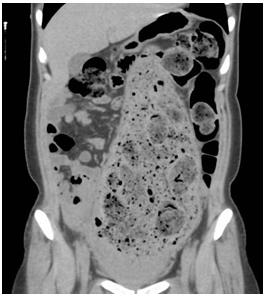

照片6:腹部CT

乙狀結(jié)腸出現(xiàn)明顯擴(kuò)張,2周的糞便鑲嵌其中。乙狀結(jié)腸上部將肝下方,胃和橫結(jié)腸向上方擠壓,左側(cè)乙狀結(jié)腸下方可確認(rèn)內(nèi)腔積蓄圓形糞便和氣體。

通常,結(jié)腸直徑超過10cm后壓力差可能穿破腸壁。本病例中,結(jié)腸已經(jīng)超負(fù)荷擴(kuò)張。實(shí)際上,患者的腸道長時(shí)間擴(kuò)張,因沒有基礎(chǔ)疾病,被診斷為慢性假性腸閉塞癥。可能導(dǎo)致腸道腸肌神經(jīng)叢或粘膜下神經(jīng)叢的功能障礙。